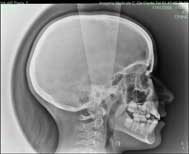

Télécrane |

| Cliché réalisé assis de profil, plus rarement de face, les oreilles fixées pour éviter de bouger. |

| La prise du cliché est quasi-instantanée. |

| Il permet à l’orthodontiste de mesurer les angles de la face et d’apprécier la position des dents. |

| Un cliché et un CD sont remis au patient. |